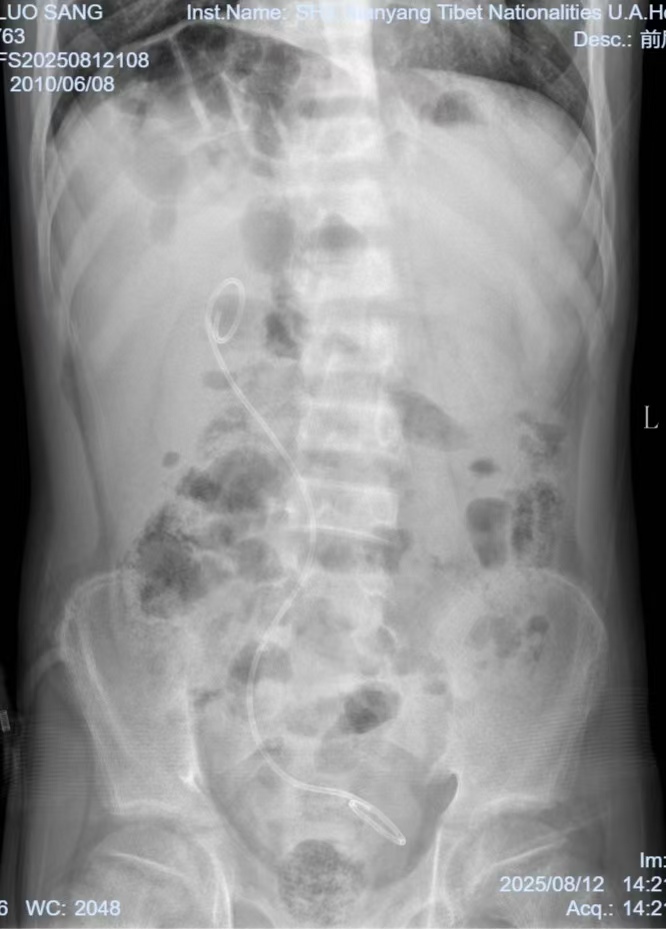

(术后复查KUB)

8月中旬,我院泌尿外科手术团队凭借娴熟的腹腔镜操作技术,精准为患者完成输尿管膀胱再植及输尿管支架置入操作。整个手术过程创伤小、术中出血量少,术后患者生命体征平稳,肾功能相关指标呈逐步改善趋势,术后恢复情况良好,现已顺利康复出院。